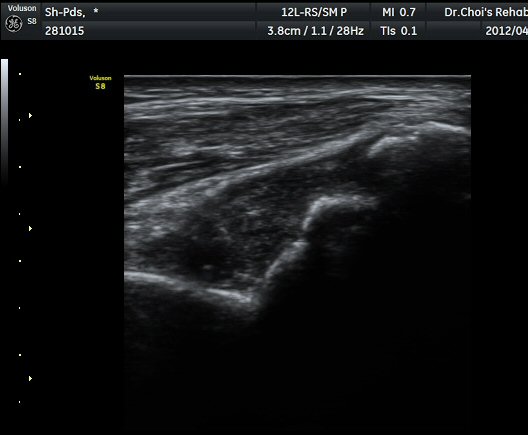

ÆÈ²ÞÄ¡ ÁÖµÎ¿Í Á¾´Ü¸é°Ë»ç À§Ä¡¿¡¼­ ŽÃÊÀÚ ¿ÜÃøÀ¸·Î ÁÖ»ç¹Ù´ÃÀ» »ðÀÔÇÏ¿©

°üÀý³» ÁÖ»çÄ¡·á ½ÃÇà(ÁÖ»ç »çÁø). °üÀý ³» ÁÖ»ç¾×ÀÌ µé¾î°¡´Â °ÍÀÌ ¶Ñ·ÈÈ÷

°üÂûµÇ¾î Áֻ簡 Àß µÇ¾úÀ½À» È®ÀÎÇÒ ¼ö ÀÖ´Ù(ÁÖ»ç µ¿¿µ»ó) .